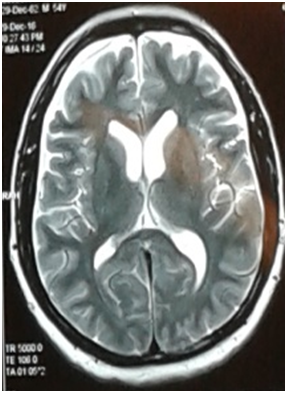

We presented a case of 55 years old businessman, known case of Hypertension and Bipolar disorder since 30 years. He was admitted thru outpatient department with irrelevant talking for 2 weeks. His family was concerned for the recent changes in the patient’s behaviour as he was not recognizing, passing stool in the bedroom, extremely irritable and agitated. He also left home for 2 days and was found unresponsive outside shopping mall. During these two weeks patient has been unpredictable, responding to internal stimuli and smiling. In hospital whenever asked about his health he usually replies: fuck you. He had history of tremors of both hands for the past 6 months. There was a history of stimulant use in the past as well. He was under treatment for bipolar disorder receiving Lithium 300mg thrice daily, Carbamazepine 200mg twice daily for the past 30 years and for hypertension on Lisinopril 5 mg daily. On examination, he was a middle-aged male, lying on bed, conscious, aggressive, not following commands, there was significant palilalia, cranial nerves were grossly intact. Motor examination showed significant increase in tone in all four limbs, no focal deficit, reflexes were normal. Plantars were flexor. No signs of meningeal irritation. No nystagmus or myoclonus appreciated. His baseline workup revealed Hb of 9.6 gm/dl (Normocytic normochromic) deranged renal parameters (urea: 150 mg/dl, Creatinine: 3.44 mg/dl), TSH of 6 Miu/L (0.4-4) Lithium levels of 3.9 mmol/L (0.4-2 mmol/L). His lithium was stopped and intravenous hydration was started. EEG and MRI Brain were done. EEG showed generalized epileptiform discharges. MRI brain showed frontal cortical atrophy, no post contrast enhancement. CSF studies were normal. HIV and VDRL serologies were negative. Patient was started on Acyclovir and Sodium valproate for epileptiform discharges. He received Haloperidol and later, kept on Quitiapine (25 mg twice a day) for agitation. During the three days of hospital stay there was no improvement in his condition. He remained encephalopathic. Repeat Lithium levels of 0.8 mmol/L (0.4-2). His HSV PCR came out as negative. His workup was sent for autoimmune encephalitis which was all negative. Thyroid antibodies were also sent with the probability of hashimoto’s encephalopathy. His anti TPO (anti-thyroid peroxidase) came out to be positive and patient was given pulse of methylprednisolone for 5 days. His symptoms improved dramatically and he was discharged after 7 days, on tapering doses of steroids. Repeat Urea 91mg/dl, Creatinine 1.88 mg/dl, Hemoglobin of 10 mg/dl. Ultrasound kidneys showed bilateral renal parenchymal disease (Figure 1).

Figure 1 T2 Weighted image showed significant frontal cortical atrophy.